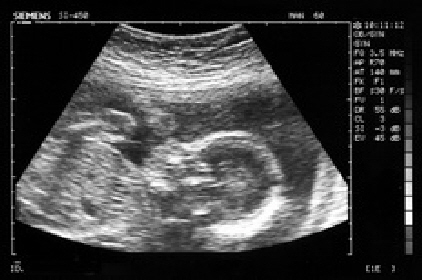

Nachdem das Dispensario neu renoviert wurde (siehe Bericht)hat sich die Stiftung nun entschlossen, das schon lang geplante Ultraschallgerät zu kaufen. Daher haben wir das bei uns noch verwaltete Geld nach Ecuador überwiesen und Monika Steffel hat zusammen mit gesammelten Spenden in Sankt Vitus, Ellwangen ausreichend Mittel zusammen, um das Gerät zu bestellen. Wenn es im Frühjahr geliefert wird, können wir bestimmt noch Bilder nachliefern

In Manglaralto wird mit Hilfe von schwedischen Geldgebern ein neues Gesundheitszentrum (Dispensario)gebaut, um auch näher an den Armenvierteln zu sein. Was dringend noch fehlt ist ein Ultraschallgerät, um bei den vielen, oft sehr jungen Schwangeren und deren ungeborenen Kindern Kontrolluntersuchungen machen zu können. Selbst bei Komplikationen ist das nächste Gerät zu weit entfernt, um helfen zu können!!

Ultraschall ist gerade in der Schwangerenvorsorge nicht ehr wegzudenken. Viele Probleme und auch ernstere Komplikationen lassen sich frühzeitig erkennen. Bei der Geburtsüberwachung hilft Ultraschall, das Befinden des Babys einschätzen zu können, um zu entscheiden, wann eingegriffen werden muss.